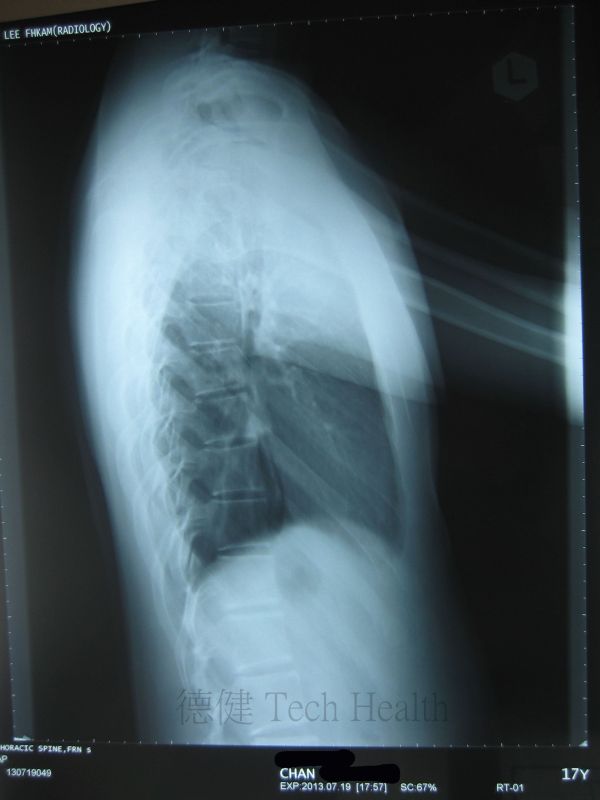

個案二 - 陳先生 18歲 - 胸椎側彎。

- 2013-7-29 患者時有困倦無力,肩背酸痛,頸胸椎活動受限,咳嗽或深呼吸時不適,胸悶胸痛,腹脹,下肢循環不佳,X片示胸椎側彎。集中治療頸胸椎及頭肩。